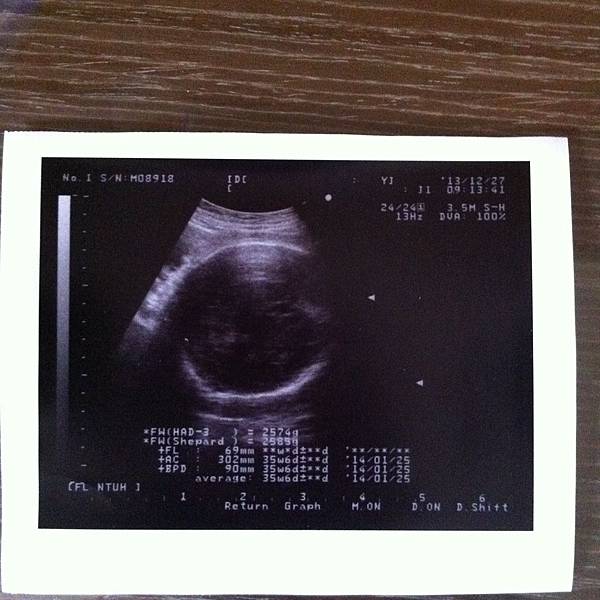

36週的寶寶已經2500多克了,很標準也很健康!